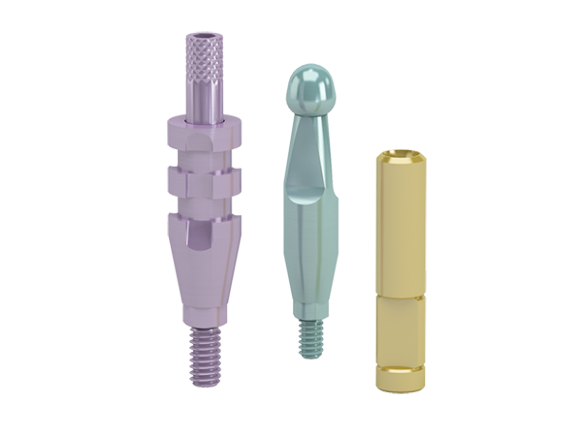

OsseoSpeed – more bone more rapidly

A chemically modified titanium surface with a unique nano scale topography that stimulates early bone healing and speeds up the bone healing process.

Conical Seal Design – a strong and stable fit

A conical connection that seals off the interior of the implant

from surrounding tissues, minimizing micromovements and microleakage.